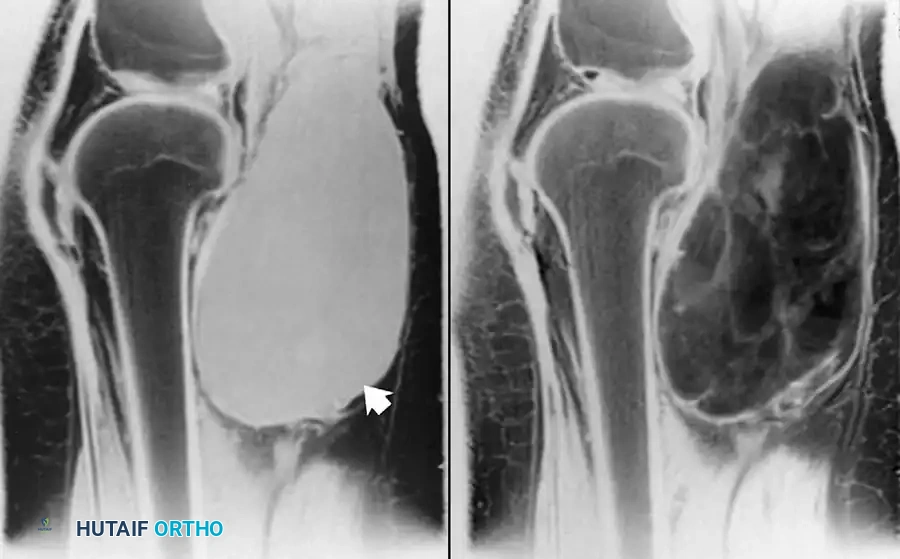

على صور الرنين المغناطيسي، يظهر التمزق الكامل كانقطاع مفاجئ في ألياف الوتر، وغالباً ما يكون مصحوباً بتراجع الوتر إلى الأعلى وتجمع للسوائل أو الدم حول منطقة الإصابة.

صورة رنين مغناطيسي توضح تمزق وتر العضلة ذات الرأسين البعيد وتراجعه